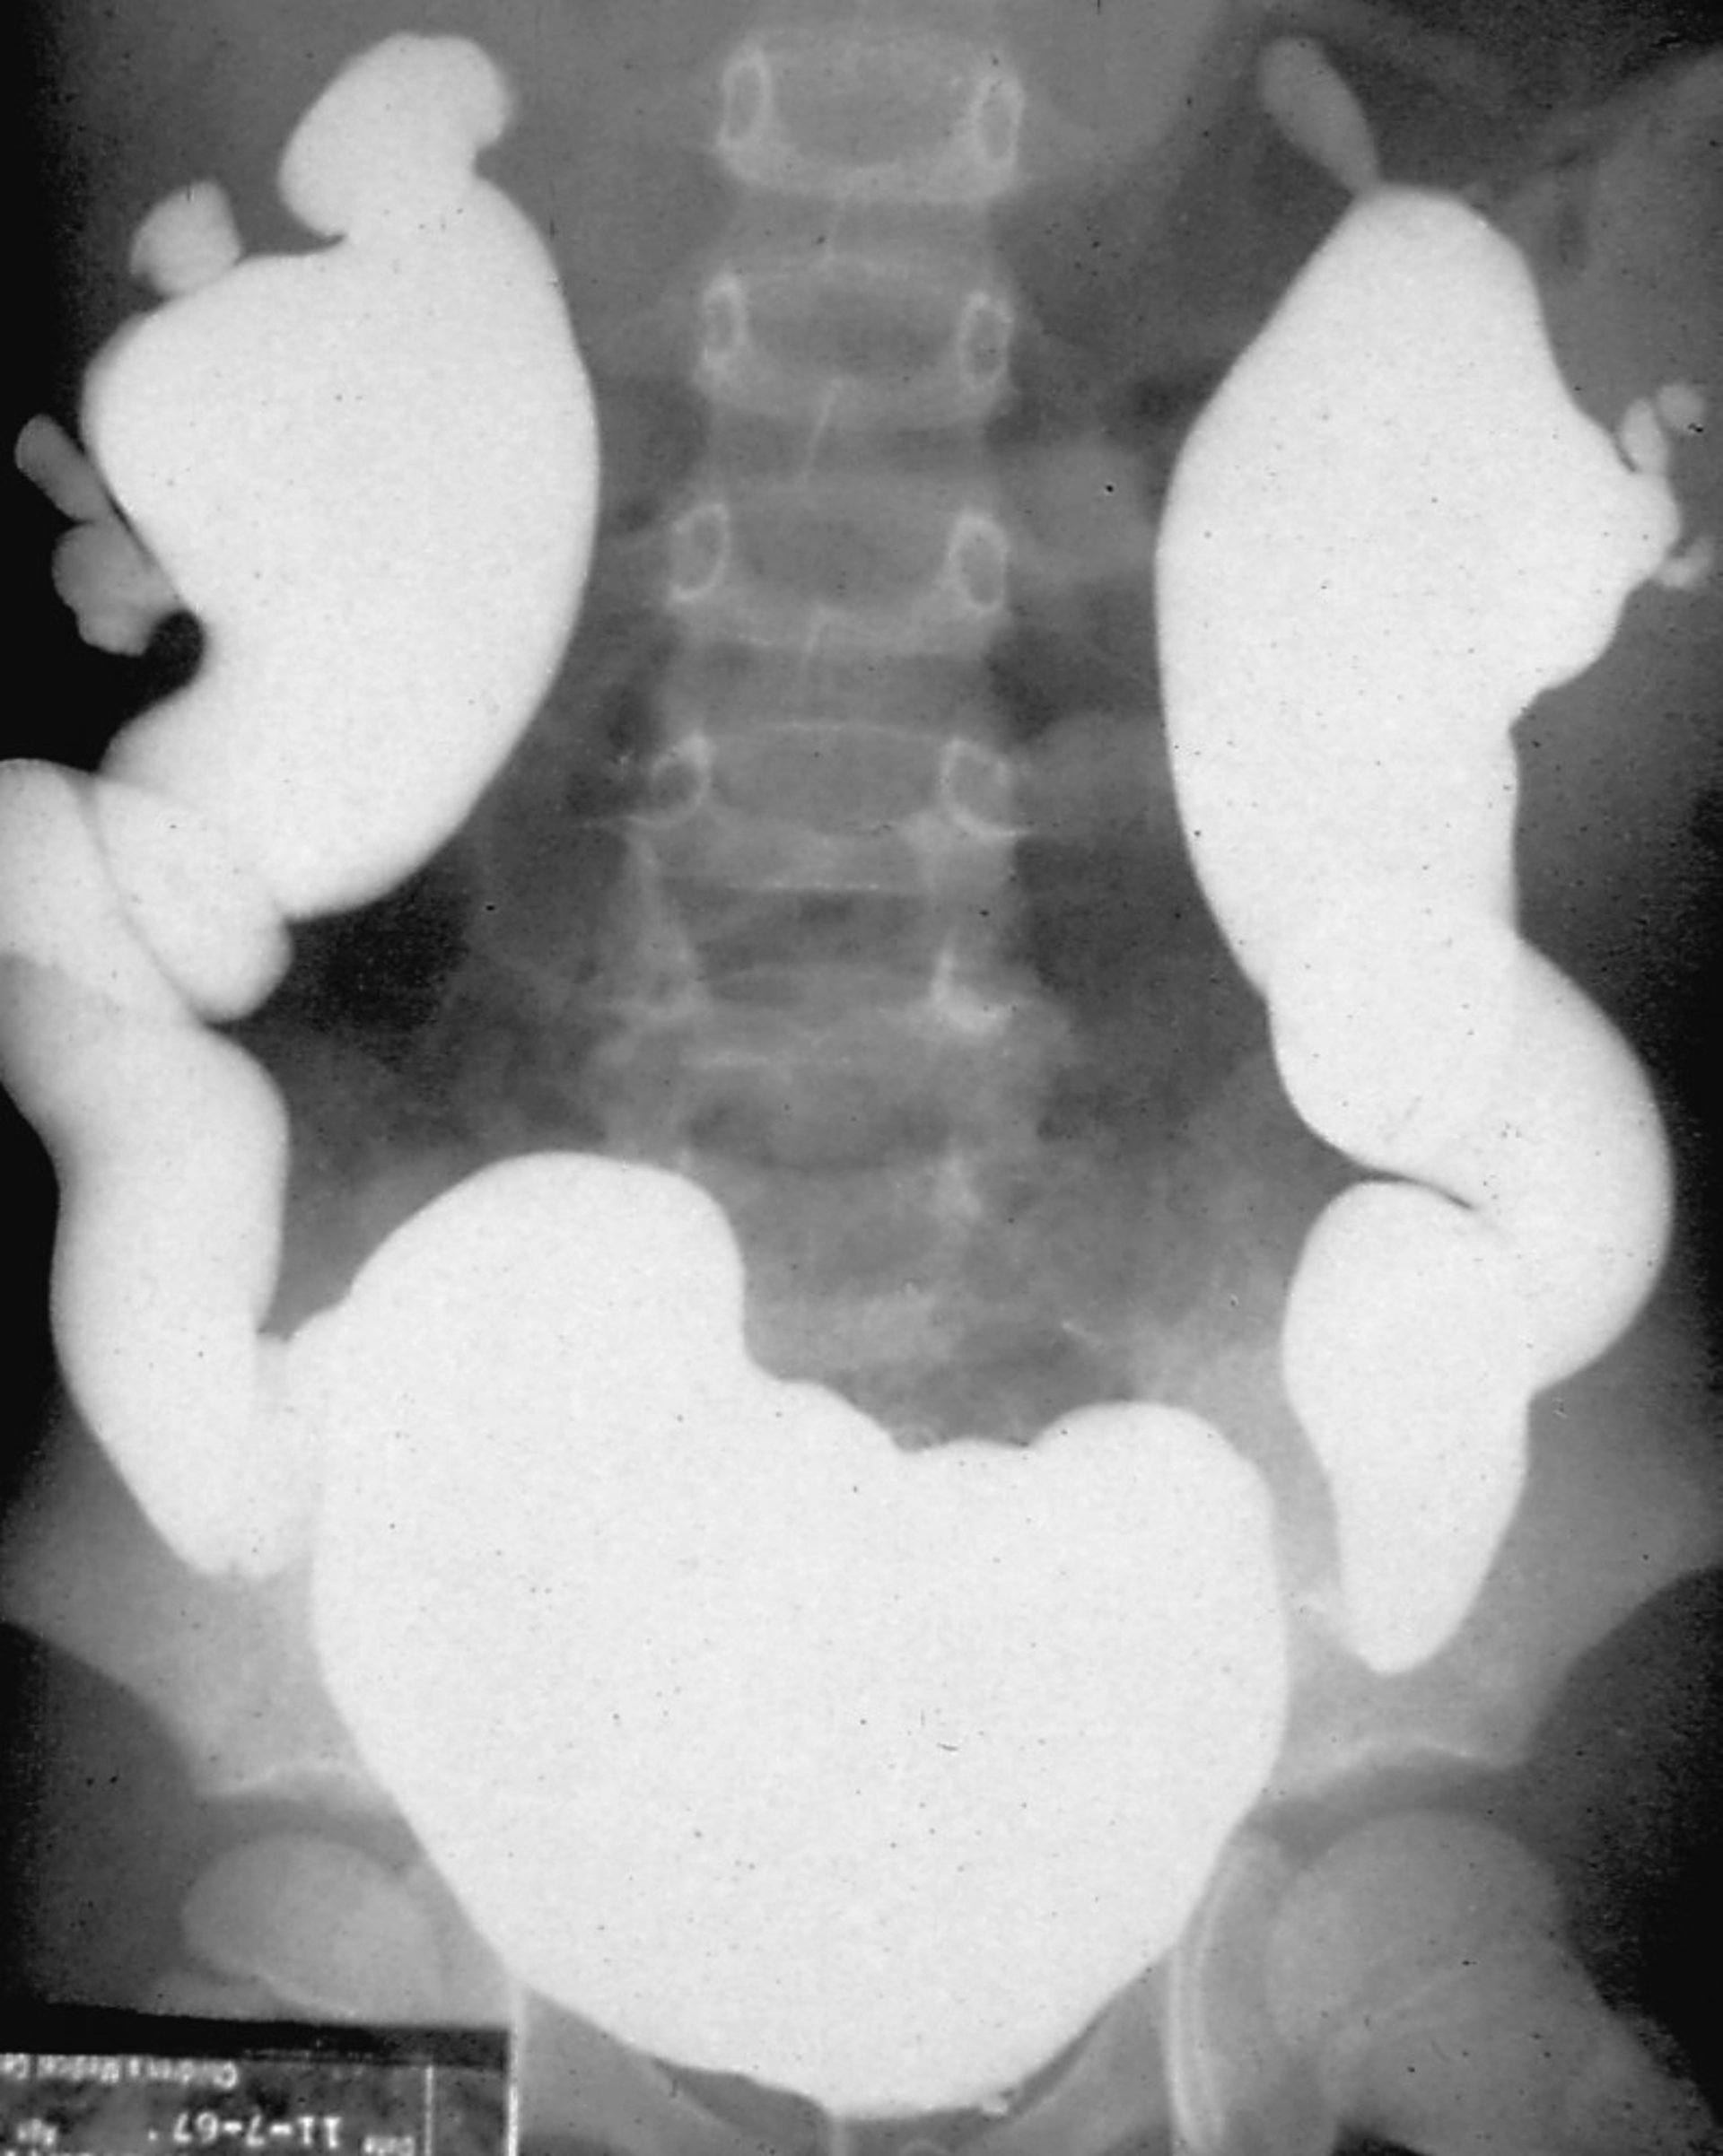

Reflux Nephropathy (Voiding Cystourethrogram)

Voiding cystourethrography is performed by filling the bladder with radiocontrast material and observing for reflux under fluoroscopy, either during the phase of bladder filling or during micturition.